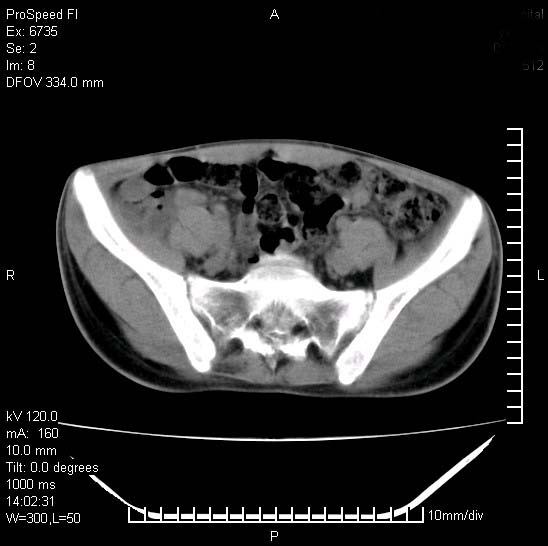

患者自诉胯部疼痛两年余,在当地服用中药,半月前至本院考虑骶髂关节结核,给予抗痨治疗。现发展至右下肢疼痛明显,活动受限,以膝关节处明显,拍膝关节平片无明显异常。

两侧骶骼关节改变,考虑强直性脊炎

左侧骶髂关节面限局性骨破坏,边缘硬化关节腔见钙化物;不出外tb

考虑强直性脊炎,建议查hla-b27

右侧骶髂关节也有类似改变,只是较左侧轻,首先考虑强直性脊柱炎,不除外结核,建议作hla-b27检查。

典型强脊炎改变,髋关节亦有累及

符合强直性脊柱炎表现。